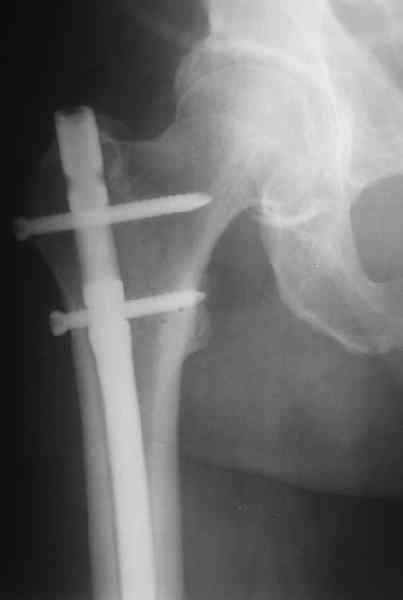

Удалили ластину без проблем. Выявилась значительная подвижность. В этих условиях сразу пропала мотивация к постепенной коррекции аппаратом. Попробовал восстановить длину, введя между отломками spreader. Отчасти удалось. Тогда защили рану, наложили спицевой дистрактор (2 спицы в дистальный отдел и 1 вверху). после этого был убран и спонгиозный винт. И сделали антгерадное штифтование, как говорится, "по принятой в

клинике методике".

Дополнительные доступы для введения гвоздя и проксимальных винтов понадобились, но они маленькие, по 1 см. Нижние винты ввели прямо между швами. Суставы дополнительно не травмировали, и даже ввели гвоздь не через f. piriformis, а через большой вертел.

Длину восстановили, возможно, даже с изьбытком, ну да динамизируем пораньше. Введенные в овальное отверстие дистальые винты имеют угловую стабильность. Снимки приложены. Заранее спасибо за критику и комментарии.